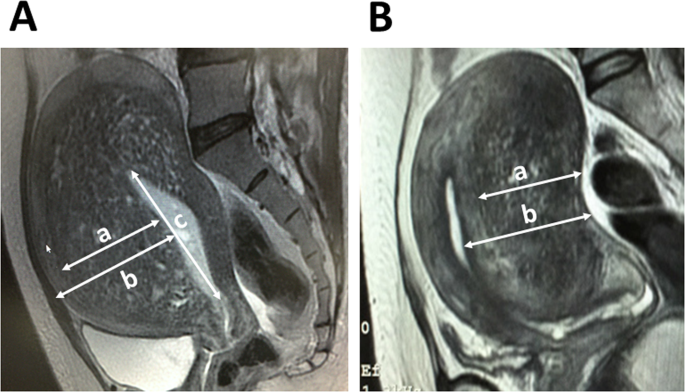

Subtype I Intrinsic Adenomyosis Is An Independent Risk Factor For Dienogest Related Serious Unpredictable Bleeding In Patients With Symptomatic Adenomyosis Scientific Reports